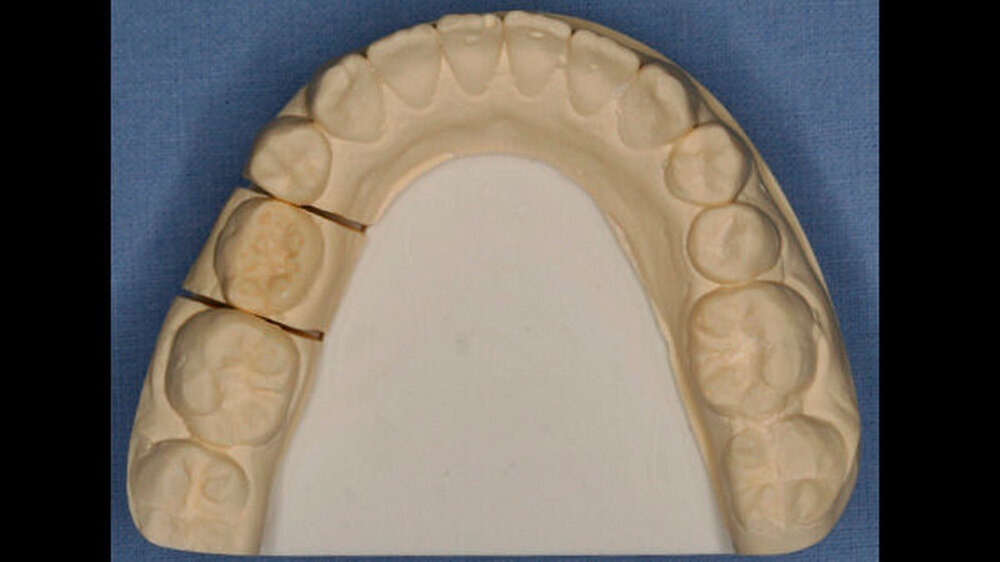

An Zahn 11 zeigte sich im inzisalen Drittel zusätzlich eine runde Schmelzopazität mit geringfügiger Hypoplasie (Abbildung 3), beides waren die Folge eines Frontzahntraumas im Milchgebiss. Darüber hinaus befand sich im zervikalen Drittel des gleichen Zahns eine rillenförmige Hypoplasie im Schmelz, höchstwahrscheinlich durch denselben Unfall verursacht (Abbildung 3).